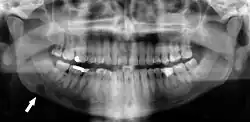

| Dental panoramic radiograph showing Stafne defect in the right mandible, below the inferior alveolar nerve canal (arrowed, appears on lower left of image). This x-ray was taken for an unrelated assessment of wisdom teeth, and the Stafne defect was a chance finding. | |

Stafne bone cavity seen on axial CT